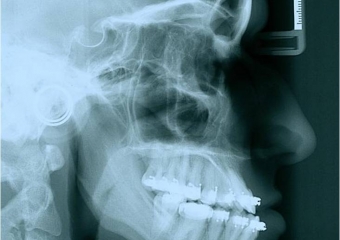

Telerradiografia após a cirurgia - Clínica Cliniface

Telerradiografia após a cirurgia